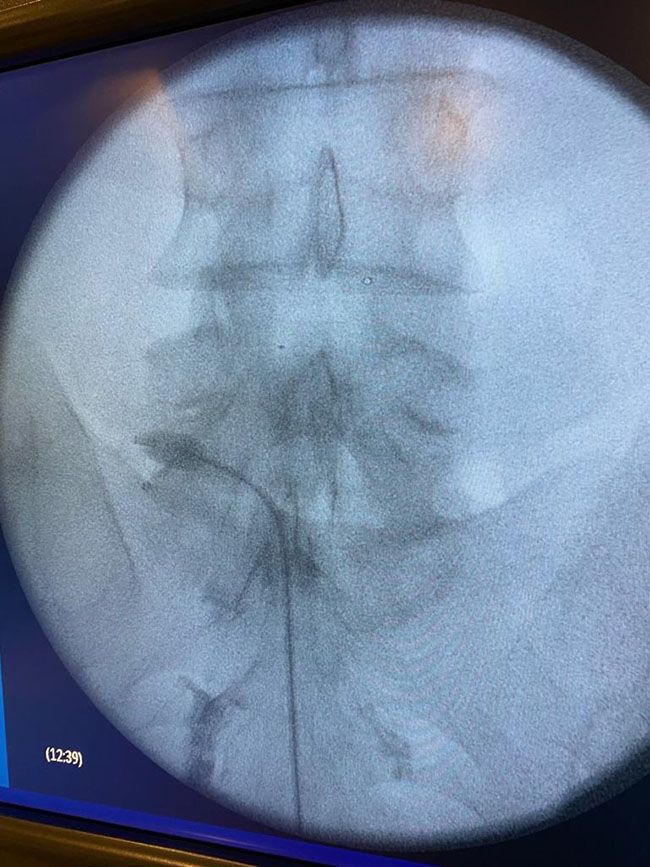

Foto: Balón para el tratamiento de la estenosis

Los Dres. Sergio Núñez Moreno y Rosario Tato Arias, anestesiólogos del Hospital El Bierzo, han sido los encargados de realizar los dos primeros casos de su centro sanitario con un nuevo sistema de navegación epidural con un catéter dirigible que incorpora un balón en el extremo distal para el tratamiento de pacientes con estenosis de tipo foraminal.  El dispositivo utilizado en este proceso ha sido proporcionado por la empresa española Cardiva, la única que lo suministra en nuestro país, y ha comenzado a utilizarse este mismo año.